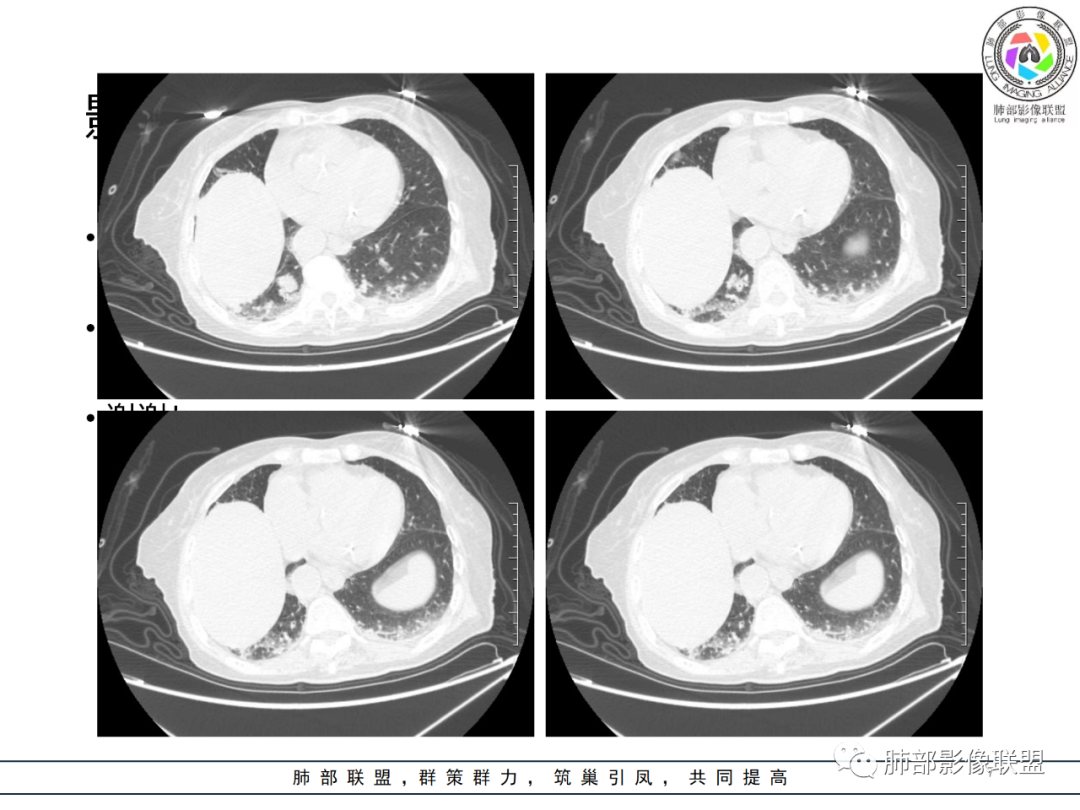

老年女性 3个月前发热,双肺支气管血管束增粗改变。3个月后再次发热,影像见双肺广泛支气管血管束明显增粗,较前进展,并延续进入纵隔,另外增强见双肾周增多软组织密度,左肾明显且肾门处形成肿块样改变。综合考虑肿瘤性病变可能性大,1.小圆细胞肿瘤类病变,淋巴瘤?2 全身组织细胞类病变,如ECD,需要看看骨组织有无问题。3 左肾恶性肿瘤并淋巴道播散,如弥漫性尿路上皮癌。最后考虑 淋巴瘤>ECD>左肾恶性肿瘤并转移。

82岁女性,反复发热入院,查外周血白细胞升高,抗生素治疗可缓解,支持细菌感染性发热,结合肾脏肿瘤,考虑泌尿系感染发热;CT提示双肺多发毛玻璃影,右下肺多发大结节影,3月复查,双上肺毛玻璃影/混合毛玻璃影增多,部分呈点晕征,右下肺多发肿块,可见支气管穿行,双下肺中轴间质增厚,左肾占位,肺部病变考虑:1.淋巴瘤 2.肾癌肺转移

右肺下叶近胸膜面多个实性结节,复查体积明显增大,多个新增实性及混合磨玻璃结节,边缘晕征,左肾及肾上腺占位,考虑囊性肾癌肺内、肾上腺转移。

右肾肾上腺,左肾及肾周软组织,脾脏可疑病变,双肺结节斑片支气管血管束叶间裂分布。一元考虑大B淋巴瘤多器官浸润。鉴别小细胞,尿路上皮癌转移,igg4

如果说两肺病变生就一张“大众脸”,但腹部异常影像却带给我们一些重要线索! 双肾病变变现为浸润性累及肾周、延及深静脉,而非典型膨胀性,低密度少血供,腹膜后肿大的淋巴结同样强化不明显,这些都符合典型的浸润性肾淋巴瘤的影像表现。注意患者肾上腺低密度结节影及脾脏多发结节影,脾脏恶性肿瘤尤以淋巴瘤最为常见!

结合肺部的分析,临床LDH升高等,我们有理由怀疑其全身系统性疾病—“淋巴瘤”。